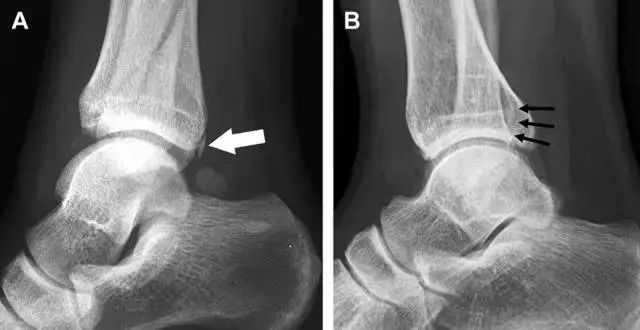

胫骨后踝骨折

涉及到三角韧带和外侧副韧带(LCL)的复杂性骨折常常不难发现,尤其是存在表面软组织肿胀时。然而,后胫腓韧带牵拉引起的胫骨后踝骨折则很难发现。这些骨折大小不一(图 2),却很重要,因为他们常与胫骨远端螺旋骨折有关,或者是三踝骨折的一部分。

图 2 胫骨后踝骨折。A 侧位片示来源于胫骨后踝的一个小骨折碎片(箭头),因踝部扭伤导致;B 另一位跖屈损伤的患者,侧位片示一个大骨折块(箭头)。